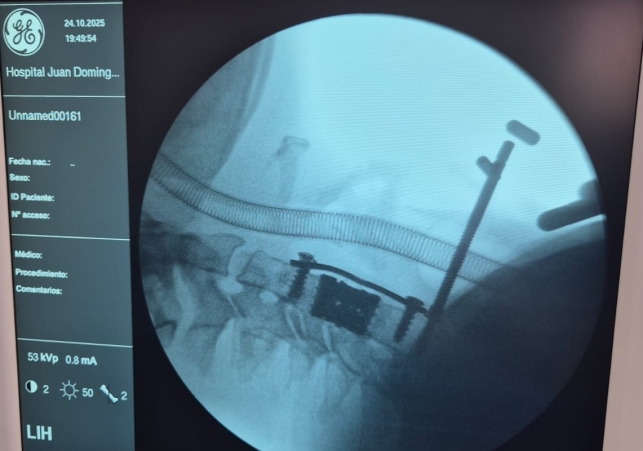

La intervención consistió en una corpectomía cervical, técnica quirúrgica destinada a resolver cuadros severos de compresión medular o radicular mediante la extracción del cuerpo vertebral afectado y su reemplazo por una prótesis especialmente diseñada, provista por el ministerio de Salud, a través de las empresas Zion–Corpomedica.

La corpectomía cervical es una práctica de alta complejidad que requiere precisión milimétrica y equipamiento de última generación. A través de una vía anterior en el cuello, se extrae uno o más cuerpos vertebrales y se reconstruye la estructura ósea mediante injerto o prótesis, liberando la presión sobre la médula espinal.